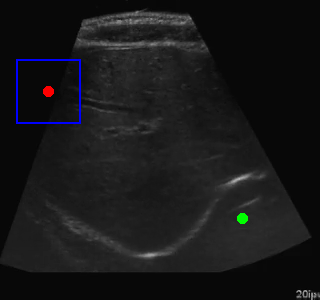

Evaluation Episode

Visualization of the agent's navigation during evaluation. The agent successfully navigates to the target center with minimal oscillations.

Example of Failure Cases

Training Episode

When tested on new data with different image characteristics, the model sometimes fails to properly identify the target regions. These failure cases highlight the importance of diverse training data that captures the full range of conditions encountered in practice.